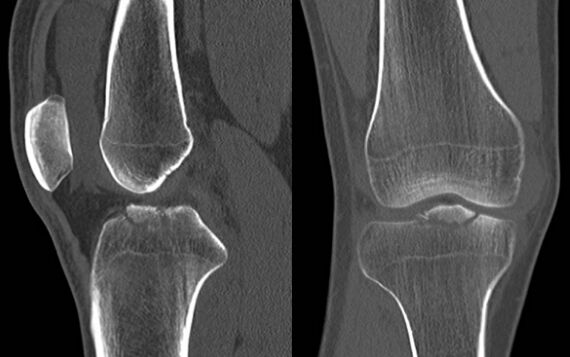

73.20歲男性病人因打球摔傷,膝部疼痛接受電腦斷層檢查,發現脛骨近端有骨折如圖。最可能合併下列何者傷害? (A)前十字韌帶(anterior cruciate ligament) (B)後十字韌帶(posterior cruciate ligament) (C)內側副韌帶(medial collateral ligament) (D)臏韌帶(patellar ligament)